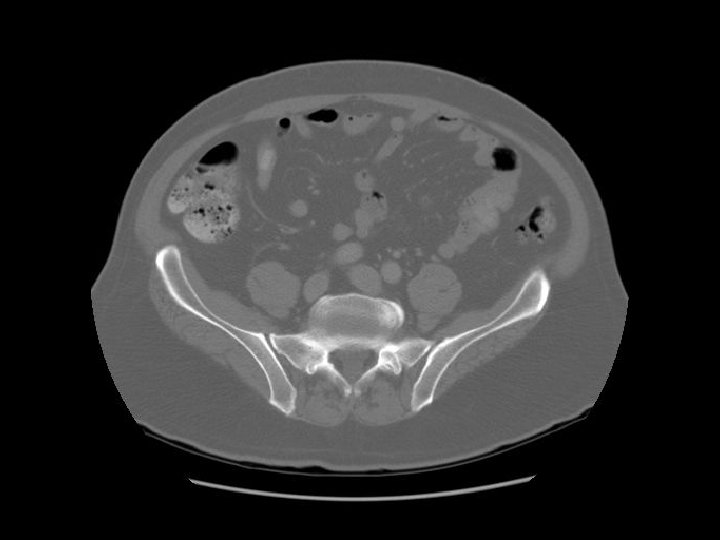

Ilium Sacrum

Arrows are pointing to the internal and external iliac veins joining to form the common iliac vein.